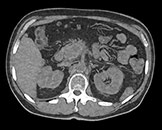

Здесь представлена серия изображений, на которых значения воксела обозначают эффективное атомное число. Эффективное атомное число может быть дробным, обозначающим какой-либо элемент, соединение или смесь. Данное число может отличаться от порядкового номера, указанного в периодической таблице. Единица для обозначения — Z.